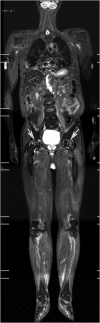

Results: STIR-WBMRI detected osteonecrosis in 15 (11.6%) patients. 38 joints were affected (mean, 2.5 per patient; range, 1-5 joints). Of the 38 joints affected by osteonecrosis, 33 had no clinical symptoms. Among the 12 patients who underwent regional MRI, STIR-WBMRI detected all 10 osteonecrotic sites seen on the regional MRI. The location, shape and size of the osteonecrotic lesions revealed on regional MRI were in accordance with those displayed on STIR-WBMRI. Of the 15 patients with osteonecrosis, 6 performed routine radiography of the affected joints and revealed no osteonecrotic lesions. Follow-up WBMRI detected new osteonecrosis in two patients whose first WBMRI revealed that there was no osteonecrosis in any skeleton.

Conclusion: In addition to displaying muscle inflammation, STIR-WBMRI can efficiently detect early multifocal osteonecrosis in the whole bodies of patients with PM/DM. Advances in knowledge: In patients with PM/DM, WBMRI which takes 12-15 min can display muscular involvement and detect early multisite osteonecrosis in the whole body at the same time. Osteonecrotic lesions revealed by WBMRI are in accordance with those displayed on regional WBMRI.